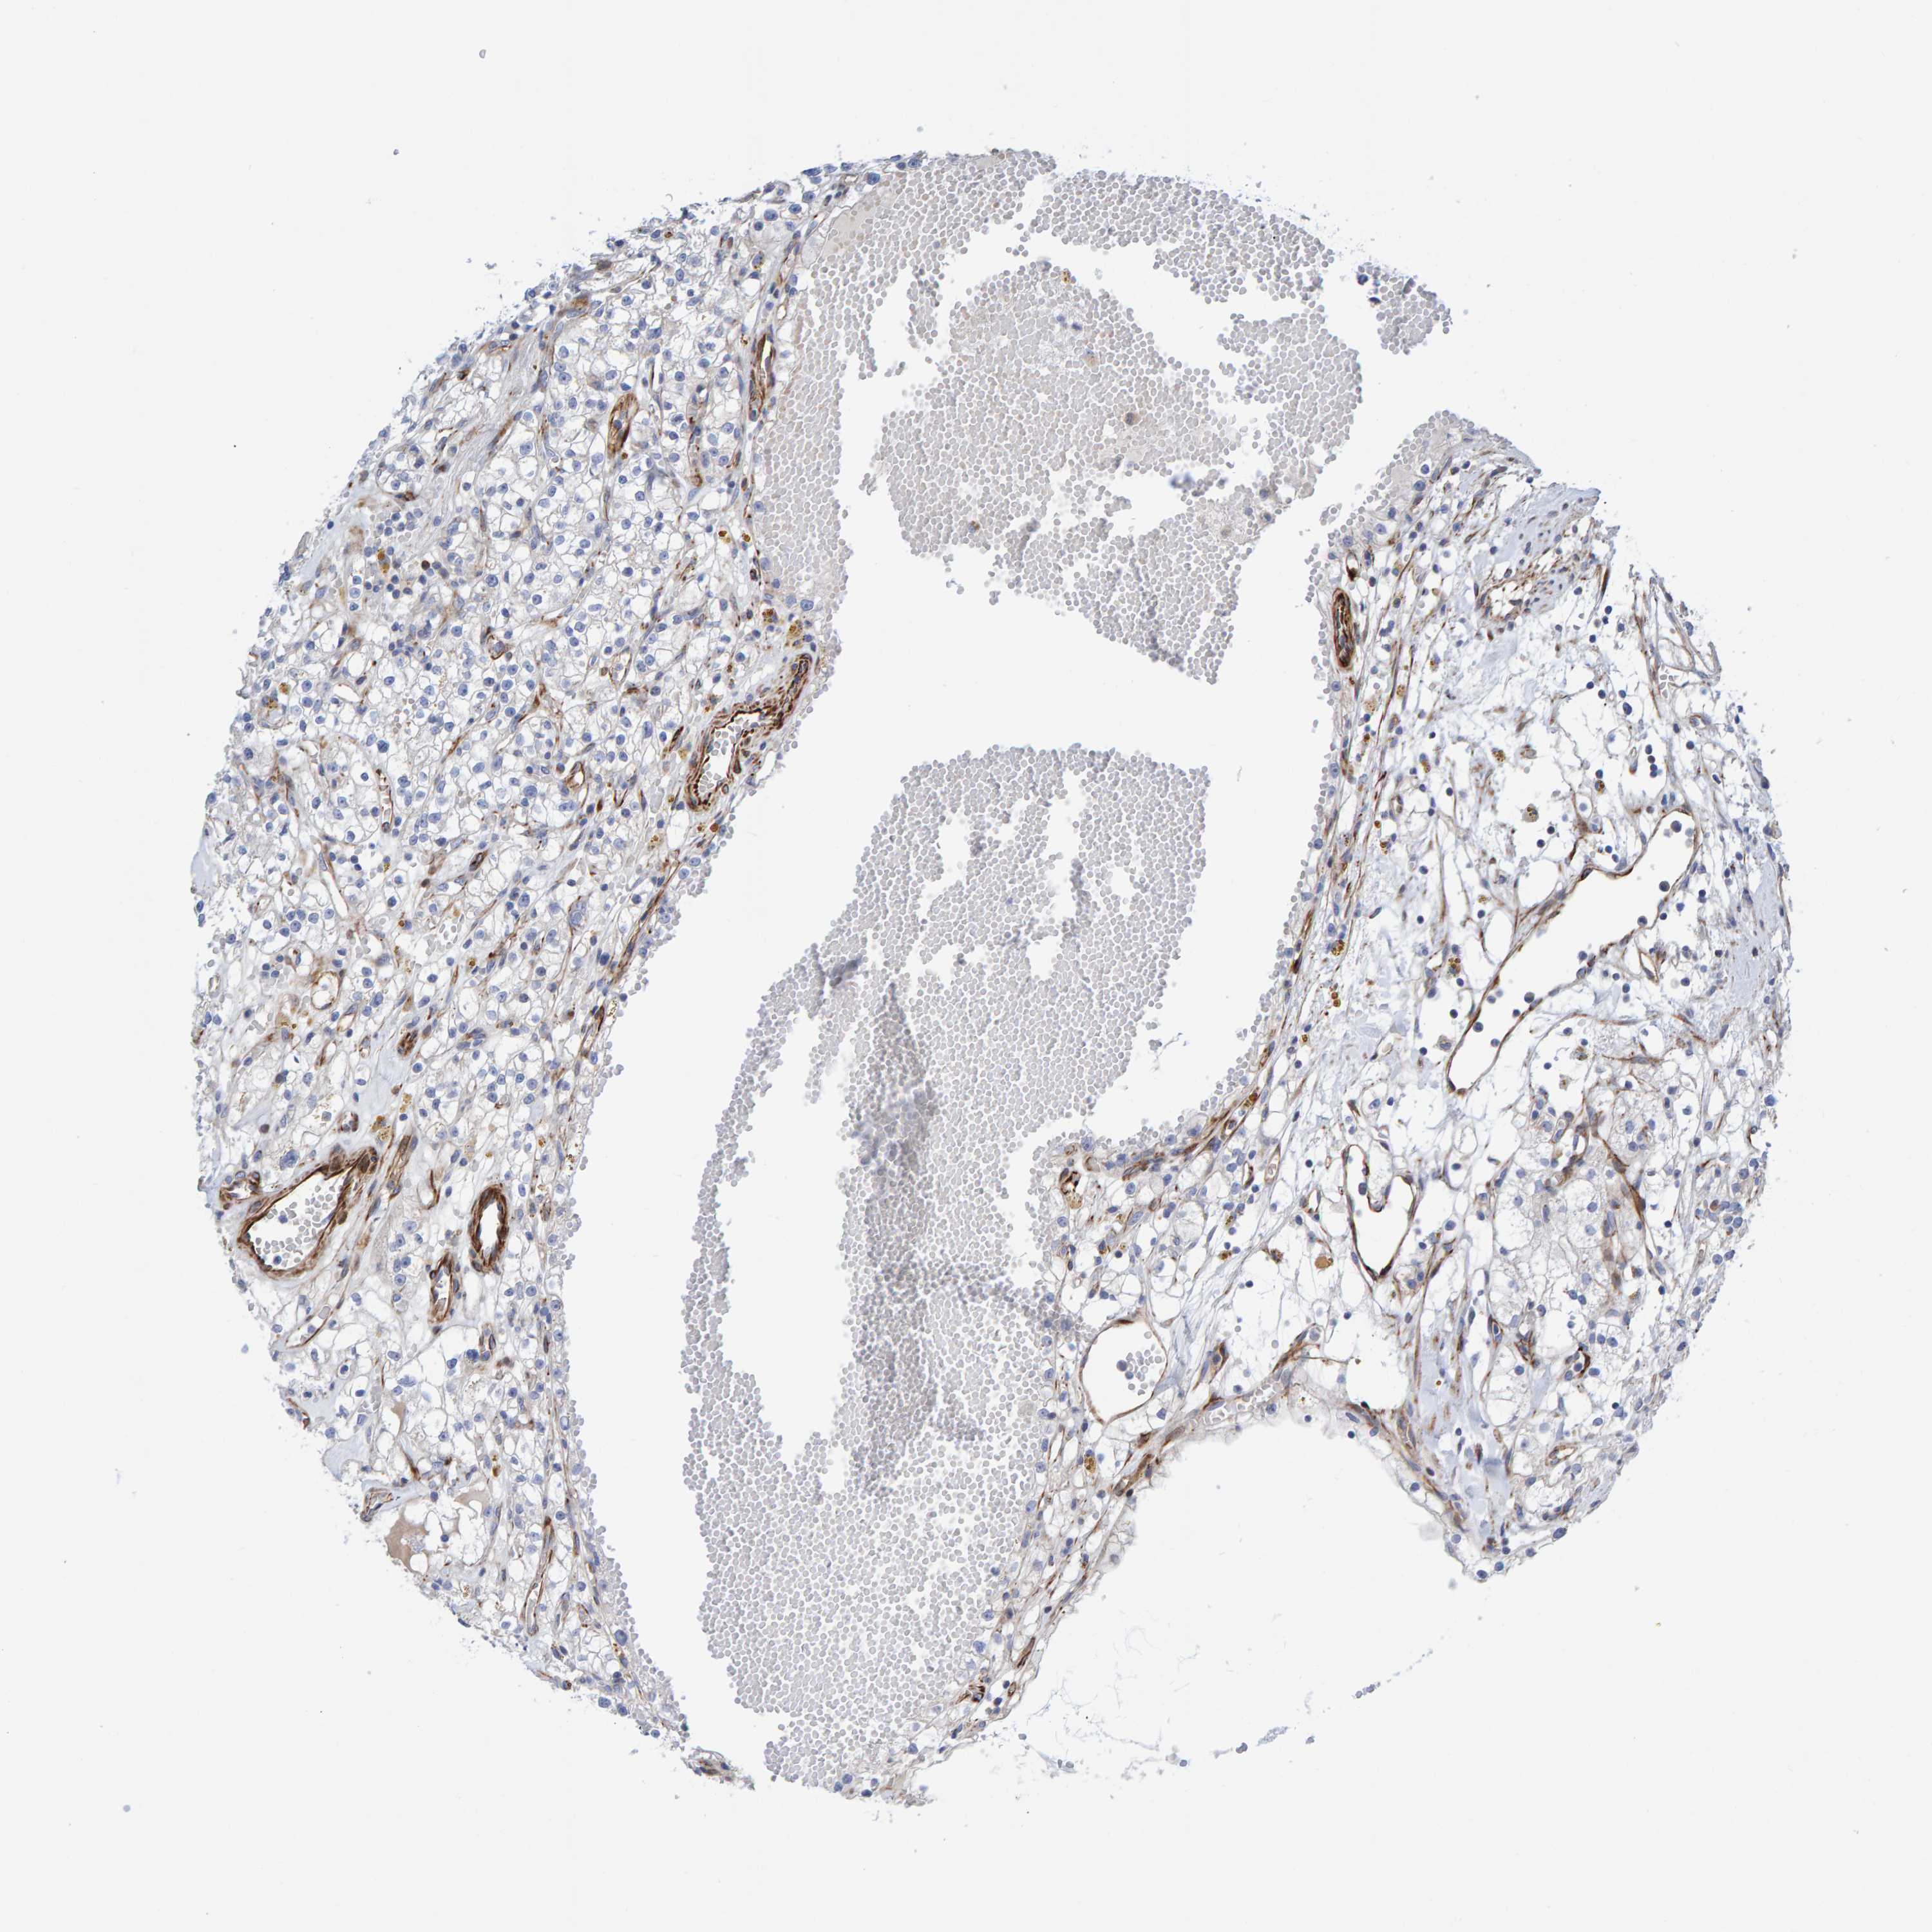

KIDNEY RENAL PAPILLARY CELL CARCINOMA (TCGA) - Interactive survival scatter ploti

The Survival Scatter plot shows the clinical status (i.e. dead or alive) for all individuals in the patient cohort, based on the same data that underlies the corresponding Kaplan-Meier plots. Patients that are alive at last time for follow-up are shown in blue and patients who have died during the study are shown in red.

The x-axis shows the expression levels (FPKM) of the investigated gene in the tumor tissue at the time of diagnosis. The y-axis shows the follow-up time after diagnosis (years). Both axes are complimented with kernel density curves demonstrating the data density over the axes. The top density plot shows the expression levels (FPKM) distribution among dead (red) and alive patients (blue). The right density plot shows the data density of the survived years of dead patients with high and low expression levels respectively, stratified using the cutoff indicated by the vertical dashed line through the Survival Scatter plot. This cutoff is automatically defined based on the FPKM cutoff that minimizes the p-score. The cutoff can be changed by dragging the vertical line or by entering a cutoff value in the square labeled "Current cut-off".

Under the Survival Scatter plot the p-score landscape (black curve; left axis) is shown together with dead median separation (red curve; right axis). Dead median separation is the difference in median mRNA expression between patients who have died with high and low expression, respectively. It is calculated as follows: median FPKM expression of dead patients with high expression - median FPKM expression of dead patients with low expression. This is intended to aid the user in visually exploring custom cutoffs and the associated p-scores and dead median separation.

Individual patient data is displayed and can be filtered by clicking on one or more of the category buttons on the top of the page. Categories describing expression level and patient information include: high, low, alive, dead, female, male and tumor stages. The scale of the x-axis can be toggled between linear and log-scale by clicking on the "x log" button. Mouse-over function shows TCGA ID, patient information and mRNA expression (FPKM) for each patient.

& Survival analysisi

Kaplan-Meier plots summarize results from analysis of correlation between mRNA expression level and patient survival. Patients were divided based on level of expression into one of the two groups "low" (under cut off) or "high" (over cut off). X-axis shows time for survival (years) and y-axis shows the probability of survival, where 1.0 corresponds to 100 percent.

POLG2 is not prognostic in Kidney Renal Papillary Cell Carcinoma (TCGA)

Best expression cut offi

Based on the FPKM value of each gene, patients were classified into two groups and association between prognosis (survival) and gene expression (FPKM) was examined. The best expression cut-off refers the FPKM value that yields maximal difference with regard to survival between the two groups at the lowest log-rank P-value. Best expression cut-off was selected based on survival analysis .

When clicking on this number, the vertical dashed line indicating cut-off, the interactive survival plot, and the Kaplan-Meier curve will be adjusted to show results based on the best expression cut-off.

: 4.34